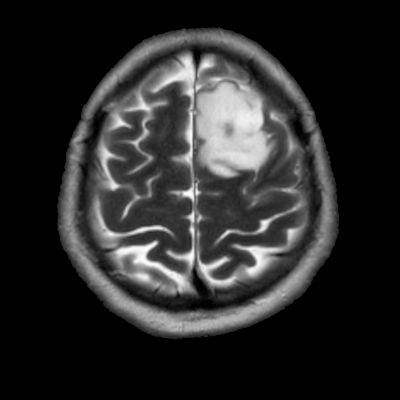

- Sol frontal kortikal-subkortikal yerleşimli aksiyel T2A görüntüde hiperintens sinyal özelliği gösteren (oklar) ve FLAIR görüntüde sinyali ağırlıklı olarak baskılanan (oklar) kitlesel lezyon izleniyor. Lezyon T1A görüntüde hipointens olup post-kontrast T1A görüntüde bu düzeyde patolojik kontrastlanma izlenmiyor (oklar).

- T1AG’de genellikle hipointens, T2AG’de ise genellikle homojen hiperintens görünümde ve kitle etkisi hafif-orta düzeydedir.Ödem genellikle eşlik etmez ya da minimal düzeydedir.

- FLAIR’de T2’ye benzer şekilde hiperintens görünür. Ancak T2–FLAIR mismatch bulgusu, bu tümör tipi için oldukça karakteristiktir.

- T2–FLAIR mismatch bulgusu, T2AG’de homojen hiperintensite ile FLAIR görüntüde santral sinyal baskılanmasının ve çevrede hiperintens halka görünümünün bulunduğu bir fenomendir. Bu bulgu, özellikle IDH-mutant, 1p/19q kodelesyonu olmayan astrositomları tanımlamada oldukça özgül bir biomarker olarak literatürde vurgulanmıştır. Ayırıcı tanıda akla gelmesi gereken oligodendrogliomlarda T2/FLAIR mismatch bulgusu genellikle görülmez.